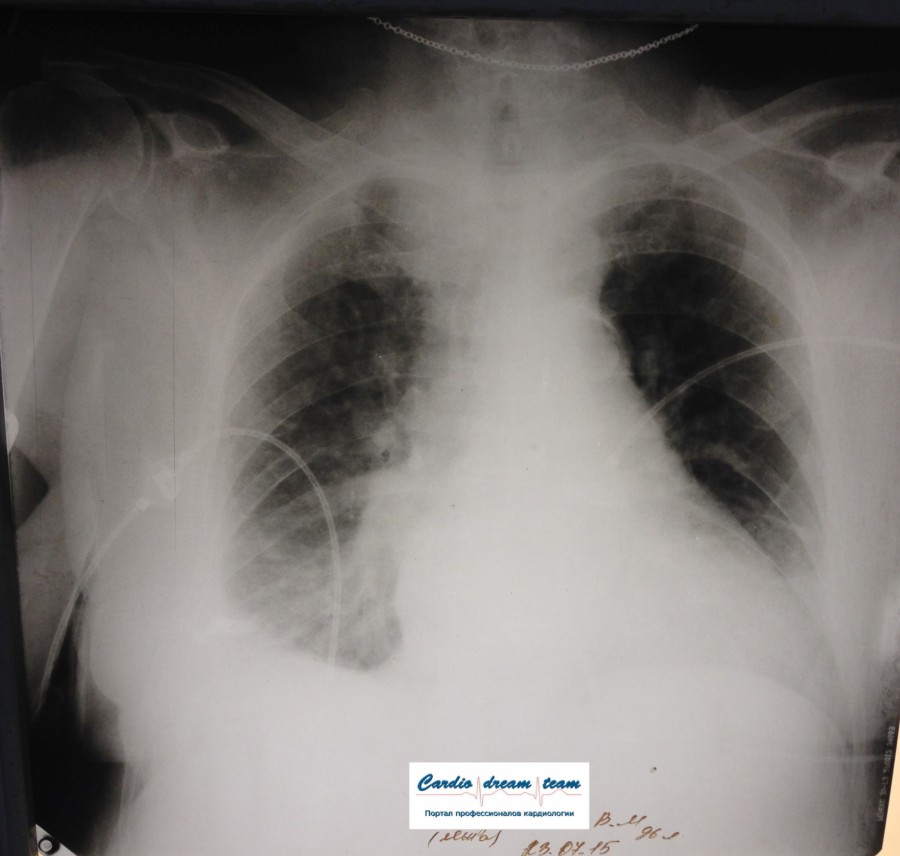

Пневмонии нет.

Не обсуждалась Дата 23-ИЮЛ-15 ОПИСАНИЕ: Проведена рентгенография органов грудной клетки в прямой проекции, положение лежа, условия ПИТ Легочные поля: неравномерно прозрачны за счет сосудистого обогащения, в базальных отделах с обеих сторон, отмечается сгущение легочного рисунка, за счет гиповентиляции, в плевральных полостях жидкость Легочный рисунок: Изменен по смешанному типу: обогащен за счет сосудистого компонента, деформирован за счет склероза. Корни: бесструктурны, расширены за счет сосудистого компонента, обогащены Синусы: определяется наличие жидкости по линии 5 ребра Сердце: широко лежит на диафрагме отмечается расширение границ сердечной тени влево, вправо экг-электроды. ЗАКЛЮЧЕНИЕ: Рентген-признаки 2-х стороннего гидроторакса с гиповентиляцией базальных сегментов.. Признаки застоя по МКК 2 степени (умеренно выраженный). Пневмосклероз. Р-признаки гипертрофии левого желудочка сердца. Склероз аорты.